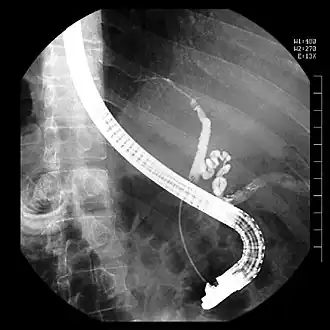

Endoscopische retrograde cholangiopancreaticografie of ERCP is een vorm van endoscopie, een medisch onderzoek om de galwegen af te beelden.

Bij een ERCP wordt een endoscoop door de mond van de patiënt naar binnen gebracht. Dit is een lange slang met glasvezel en aan het uiteinde een lens. Aan het andere uiteinde kan een videocamera worden bevestigd. Door de endoscoop kunnen verschillende instrumenten worden ingebracht. De endoscoop passeert de maag en komt dan in de twaalfvingerige darm. Daar bevindt zich de uitmonding van de galgang, die de papil van Vater wordt genoemd. Instrumenten kunnen worden opgevoerd in de papil van Vater. Als er dan contrastvloeistof in de galgang wordt gespoten, kunnen er röntgenfoto's worden gemaakt die de galgang afbeelden.

Afwijkingen die met een ERCP kunnen worden vastgesteld zijn galstenen in de galgang, een pancreaskopcarcinoom[1] of andere aandoeningen van de galgang, maar er kunnen met een ERCP ook interventies worden uitgevoerd, zoals het verwijderen van galstenen uit de galgang of het plaatsen van een stent in de galgang. Een stent is een plastic of metalen buisje dat wordt ingebracht in de galgang als die vernauwd is en is ervoor om te zorgen dat de gal naar de darm kan blijven afvloeien. Een ERCP wordt meestal door een gastro-enteroloog uitgevoerd.